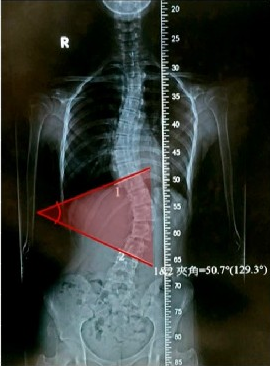

Awalnya, gadis ini gak nyangka hal buruk ini bakal jadi kenyataan. Namun, ketika sakit punggung datang menyerang dan sakitnya gak tertahankan, Ibunya langsung membawanya ke dokter. Beberapa waktu berkonsultasi dan melakukan pemindaian dengan sinar X untuk mencari tau penyebabnya, si Ibu dan gadis remaja ini sangat terkejut. Hasil yang didapat, punggung anak gadisnya meliuk-liuk seperti huruf S.

Dokter yang melakukan pemindaian X-ray mengatakan jika tulang punggung gadis itu mengalami pembengkokan yang mencapai 50 derajat. Dokter lalu membuat sebuah rekam jejak medis dan mecari kebiasaan si anak gadis. Dan, fakta si anak gadis sering banget main HP sambil tiduran membuat dokter menyimpulkan jika terjadi tekanan yang berlebihan pada tulang punggungnya hingga menyebabkan pembengkokan. Belum lagi, umur-umur 16 tahun merupakan umur pertumbuhan tulang yang membuatnya semakin mudah terbentuk.

Selain itu, dokter juga menjelaskan jika anak gadis ini jarang sekali berolahraga sehingga kekuatan otot dan tulangnya sangat lemah untuk menahan beban yang terlalu lama. Dokter yang menangani kasus ini sempat mengatakan jika kasus serupa pernah terjadi sebelumnya, tapi pembengkokannya hanya sebesar 38 derajat.